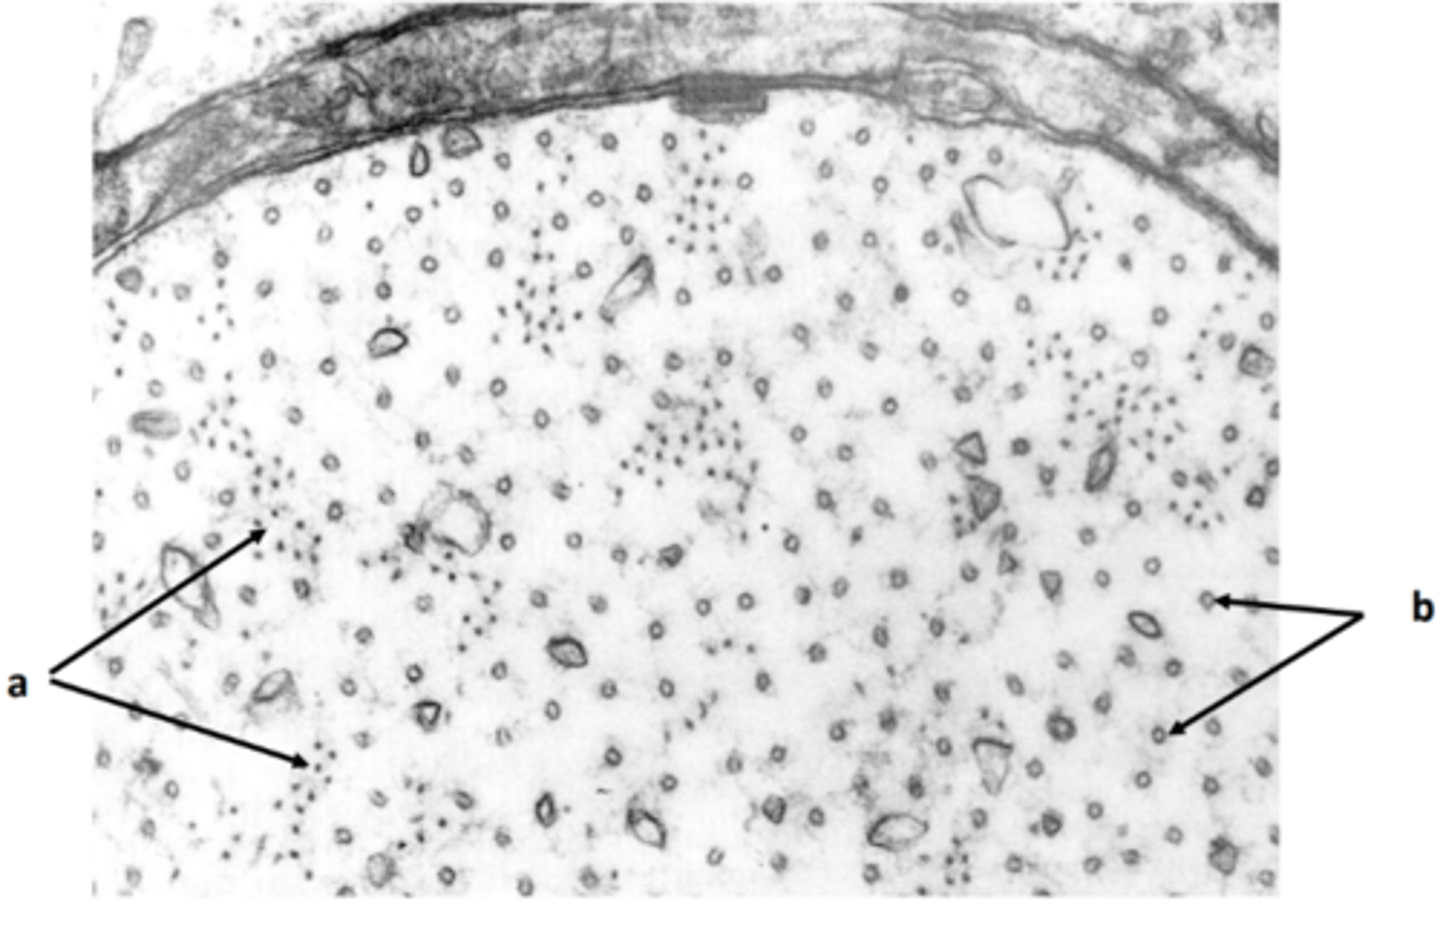

myelin sheath

a: structure

<p>a: structure</p>

schwann cell nucleus

b: structure

<p>b: structure</p>

schwann cell cytoplasm

c: structure

<p>c: structure</p>

microtubule, neurofilament, mitochondria

d: two structures present in labelled region

<p>d: two structures present in labelled region</p>